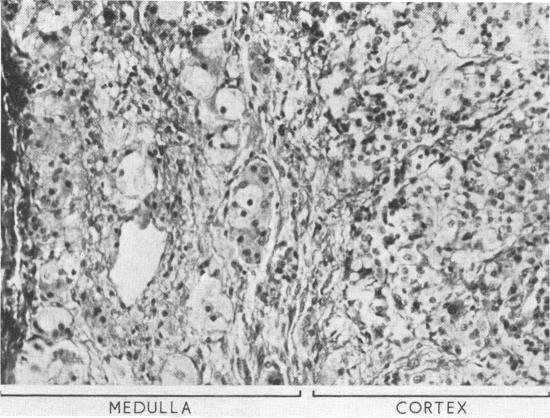

Adrenocortical atrophy and diffuse cerebral sclerosis.

A boy, diagnosed as having Addison's disease due to idiopathic atrophy of the adrenal glands at the age of 7 years, developed the first evidence of what was originally thought to be Schilder's disease' at 8 years and 10 months. He died at 9 years and 11 months. There was a very striking family history of autoimmune disorders on the mother's side. The clinical and pathological aspects of his case are outlined. Detailed studies of adrenal function during life showed a diminution in excretion of adrenal androgens and corticosteroids before therapy which was not evident from the 17-oxosteroid and 17-hydroxycorticosteroid assays in the resting state, though the initial diagnosis was based on the failure of ACTH to produce a rise in the 17-hydroxycorticosteroid excretion. No unusual or abnormal steroids were detected nor was there any disproportion between the androgen and corticosteroid excretion to suggest an adrenal enzyme deficiency. The biochemistry of the brain at necropsy revealed the changes expected in a demyelinating disorder, but the detection of abnormalities in the grey matter distinguished the condition from Schilder's disease' in which the biochemistry of the grey matter is normal. There are 12 fully documented reports of boys with adrenocortical atrophy and diffuse cerebral sclerosis, and it is thought that this rare entity is inherited as an X-linked recessive characteristic. The two likely theories of causation involve either an error of metabolism common to the adrenal cortex and the brain, or the possibility that both the adrenal and brain pathology are due to an autoimmune disorder.